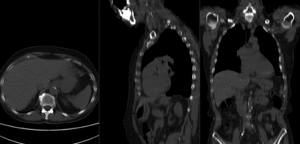

Registration Results

RegLib C20 unregistered.gif |before registration (click to enlarge)

RegLib C20 registered.gif |after affine registration (click to enlarge)

RegLib C20 registered2.gif |BSpline deformation grid (click to enlarge)